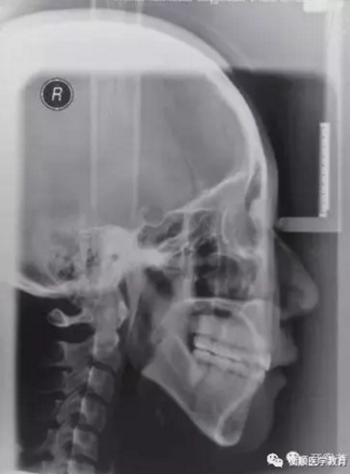

圖6 治療后頭顱側位片